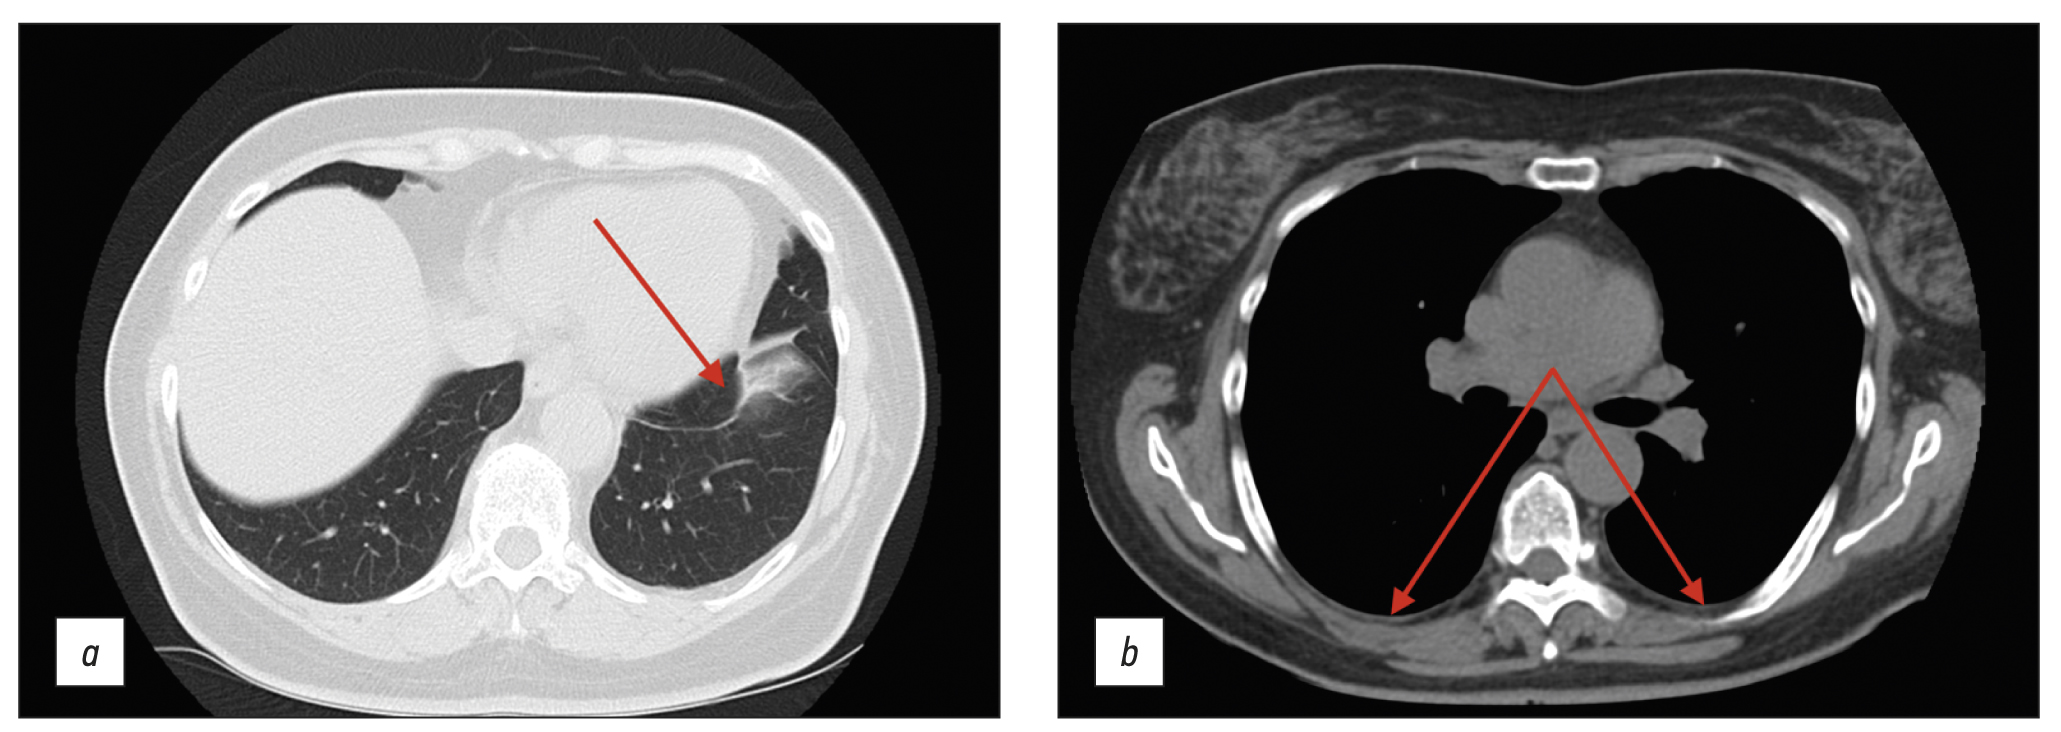

The patient was generally well in August 2020, but she began experiencing daily elevations in body temperature to 38.5°C–39°C, followed by muscular and joint pain. Antipyretics had no effect; therefore, the patient was admitted to the Infection Department inpatient unit and received antibiotics and oral and intravenous detoxification medications. The medication improved the overall condition, although the subfebrile body temperature continued in the evenings. The thoracic CT scan revealed modest effusion in the pleural cavities, bilateral bands of peribronchovascular thickening, small subsegmental compression atelectasis in the basal regions of both lungs, and elevated hemidiaphragm (Figure 1).

Fig. 1. Thoracic computed tomography scan (August 2020); axial plane: the red arrows show (a) subsegmental compression atelectasis and (b) mild pleural effusion.